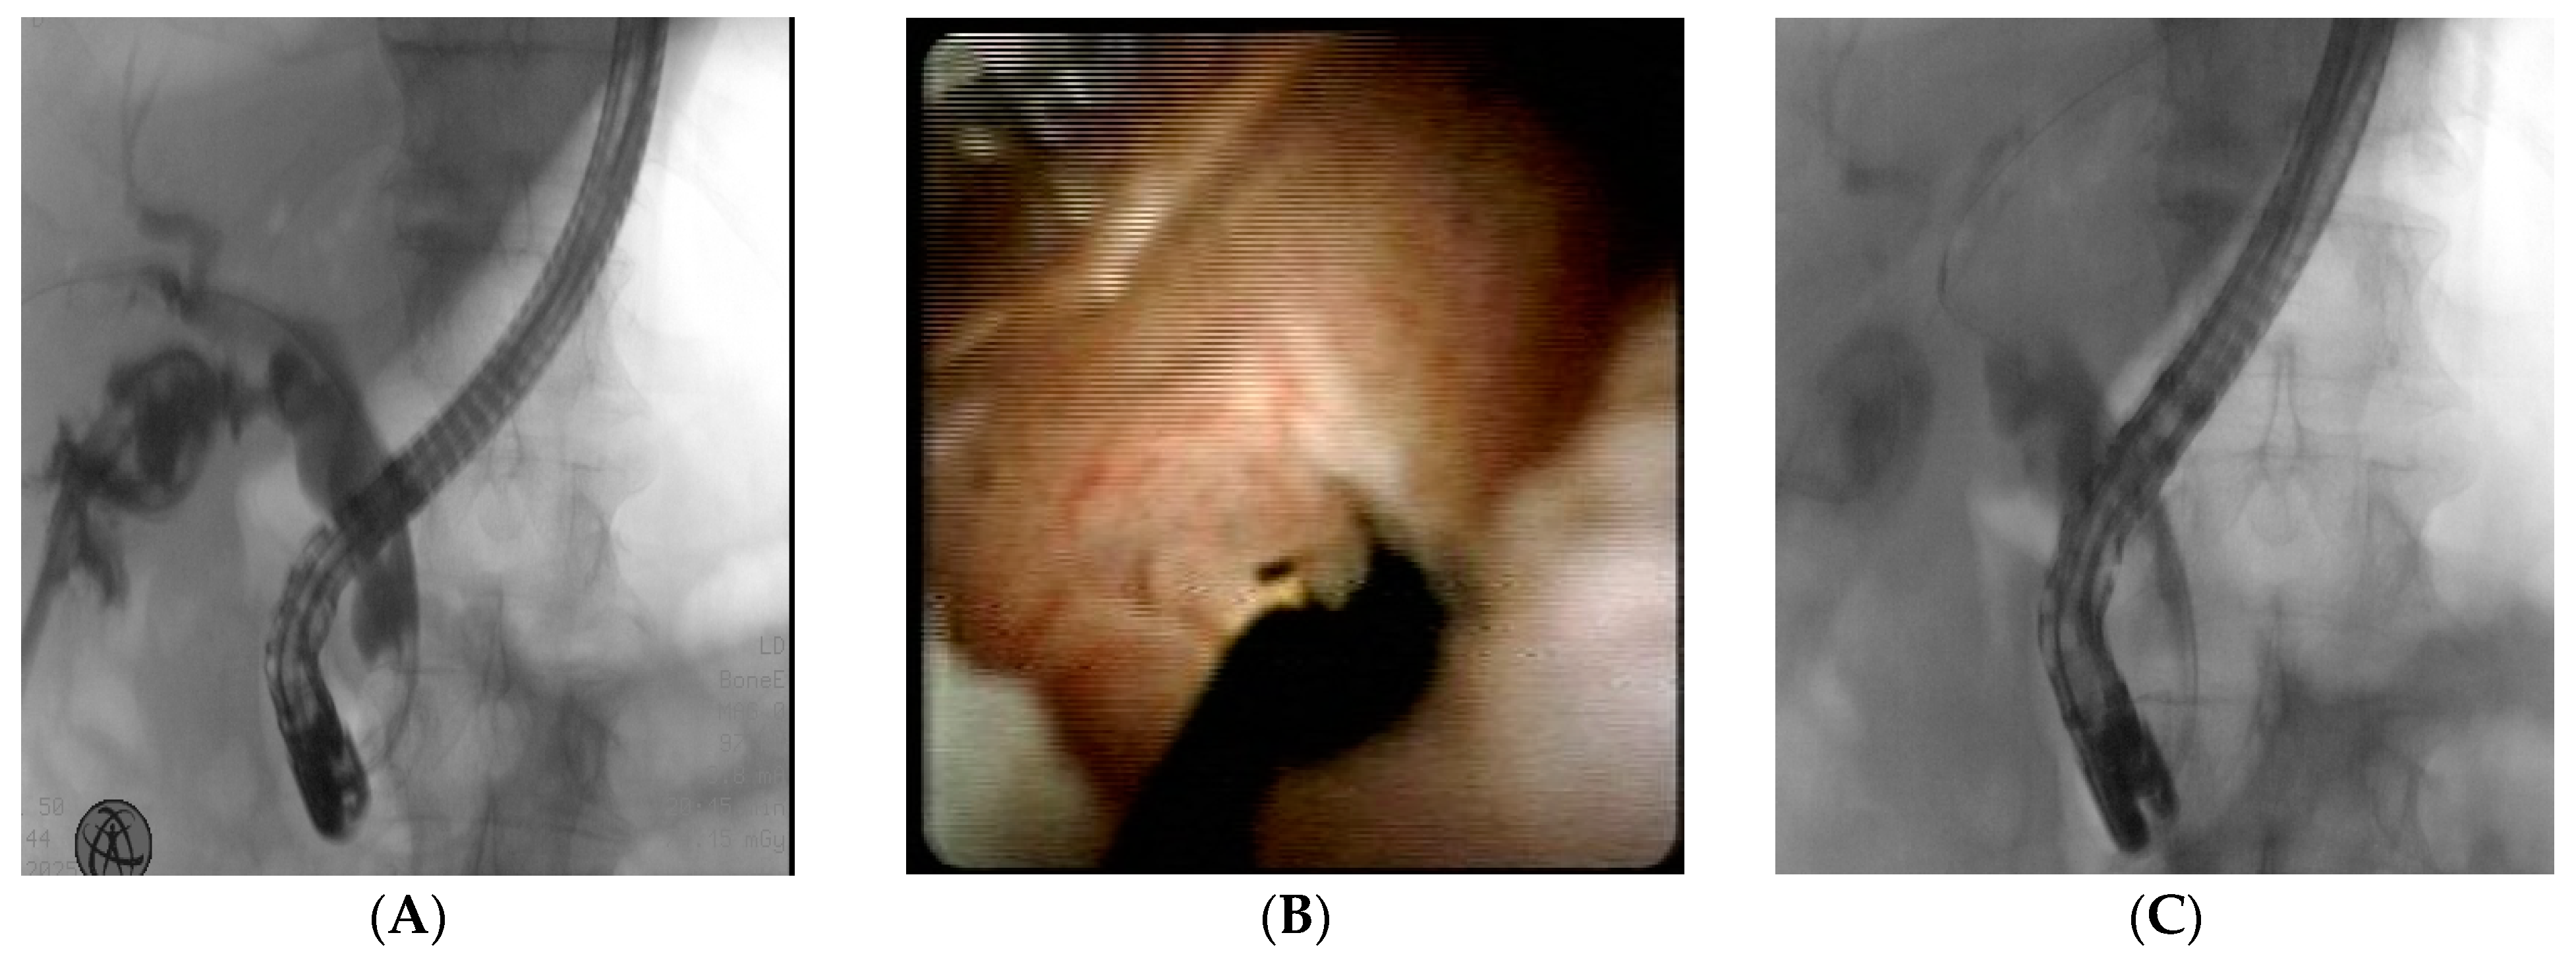

3.2. Cystic Duct Leak